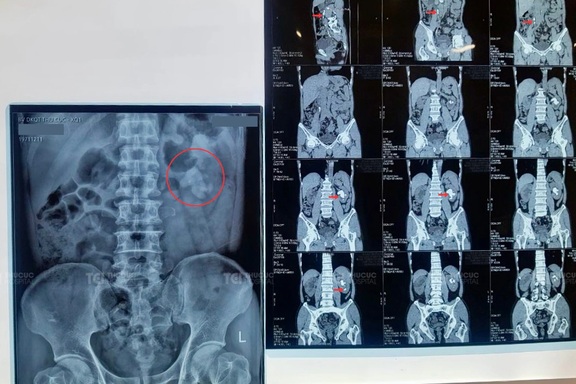

Phối hợp 3 kỹ thuật hiện đại điều trị thành công sỏi tiết niệu đa vị tríCác bác sĩ khoa Ngoại thận, tiết niệu TCI đã điều trị thành công trường hợp sỏi phức tạp đa vị trí ở cả hai thận và niệu quản, trong đó có sỏi san hô kích thước lớn bằng phác đồ kết hợp ba kỹ thuật tán sỏi nội soi tiên tiến, không mổ mở.

Hy hữu sỏi có hình dạng như quả trứng xuất hiện ở thận của chàng trai 22 tuổiSỏi bể thận ngoài xoang hình dạng cỡ quả trứng hiếm gặp được các bác sĩ khoa Ngoại thận, tiết niệu - Bệnh viện ĐKQT Thu Cúc điều trị thành công với phương pháp tán sỏi qua da bằng đường hầm nhỏ (mini), bảo tồn tối đa chức năng thận.